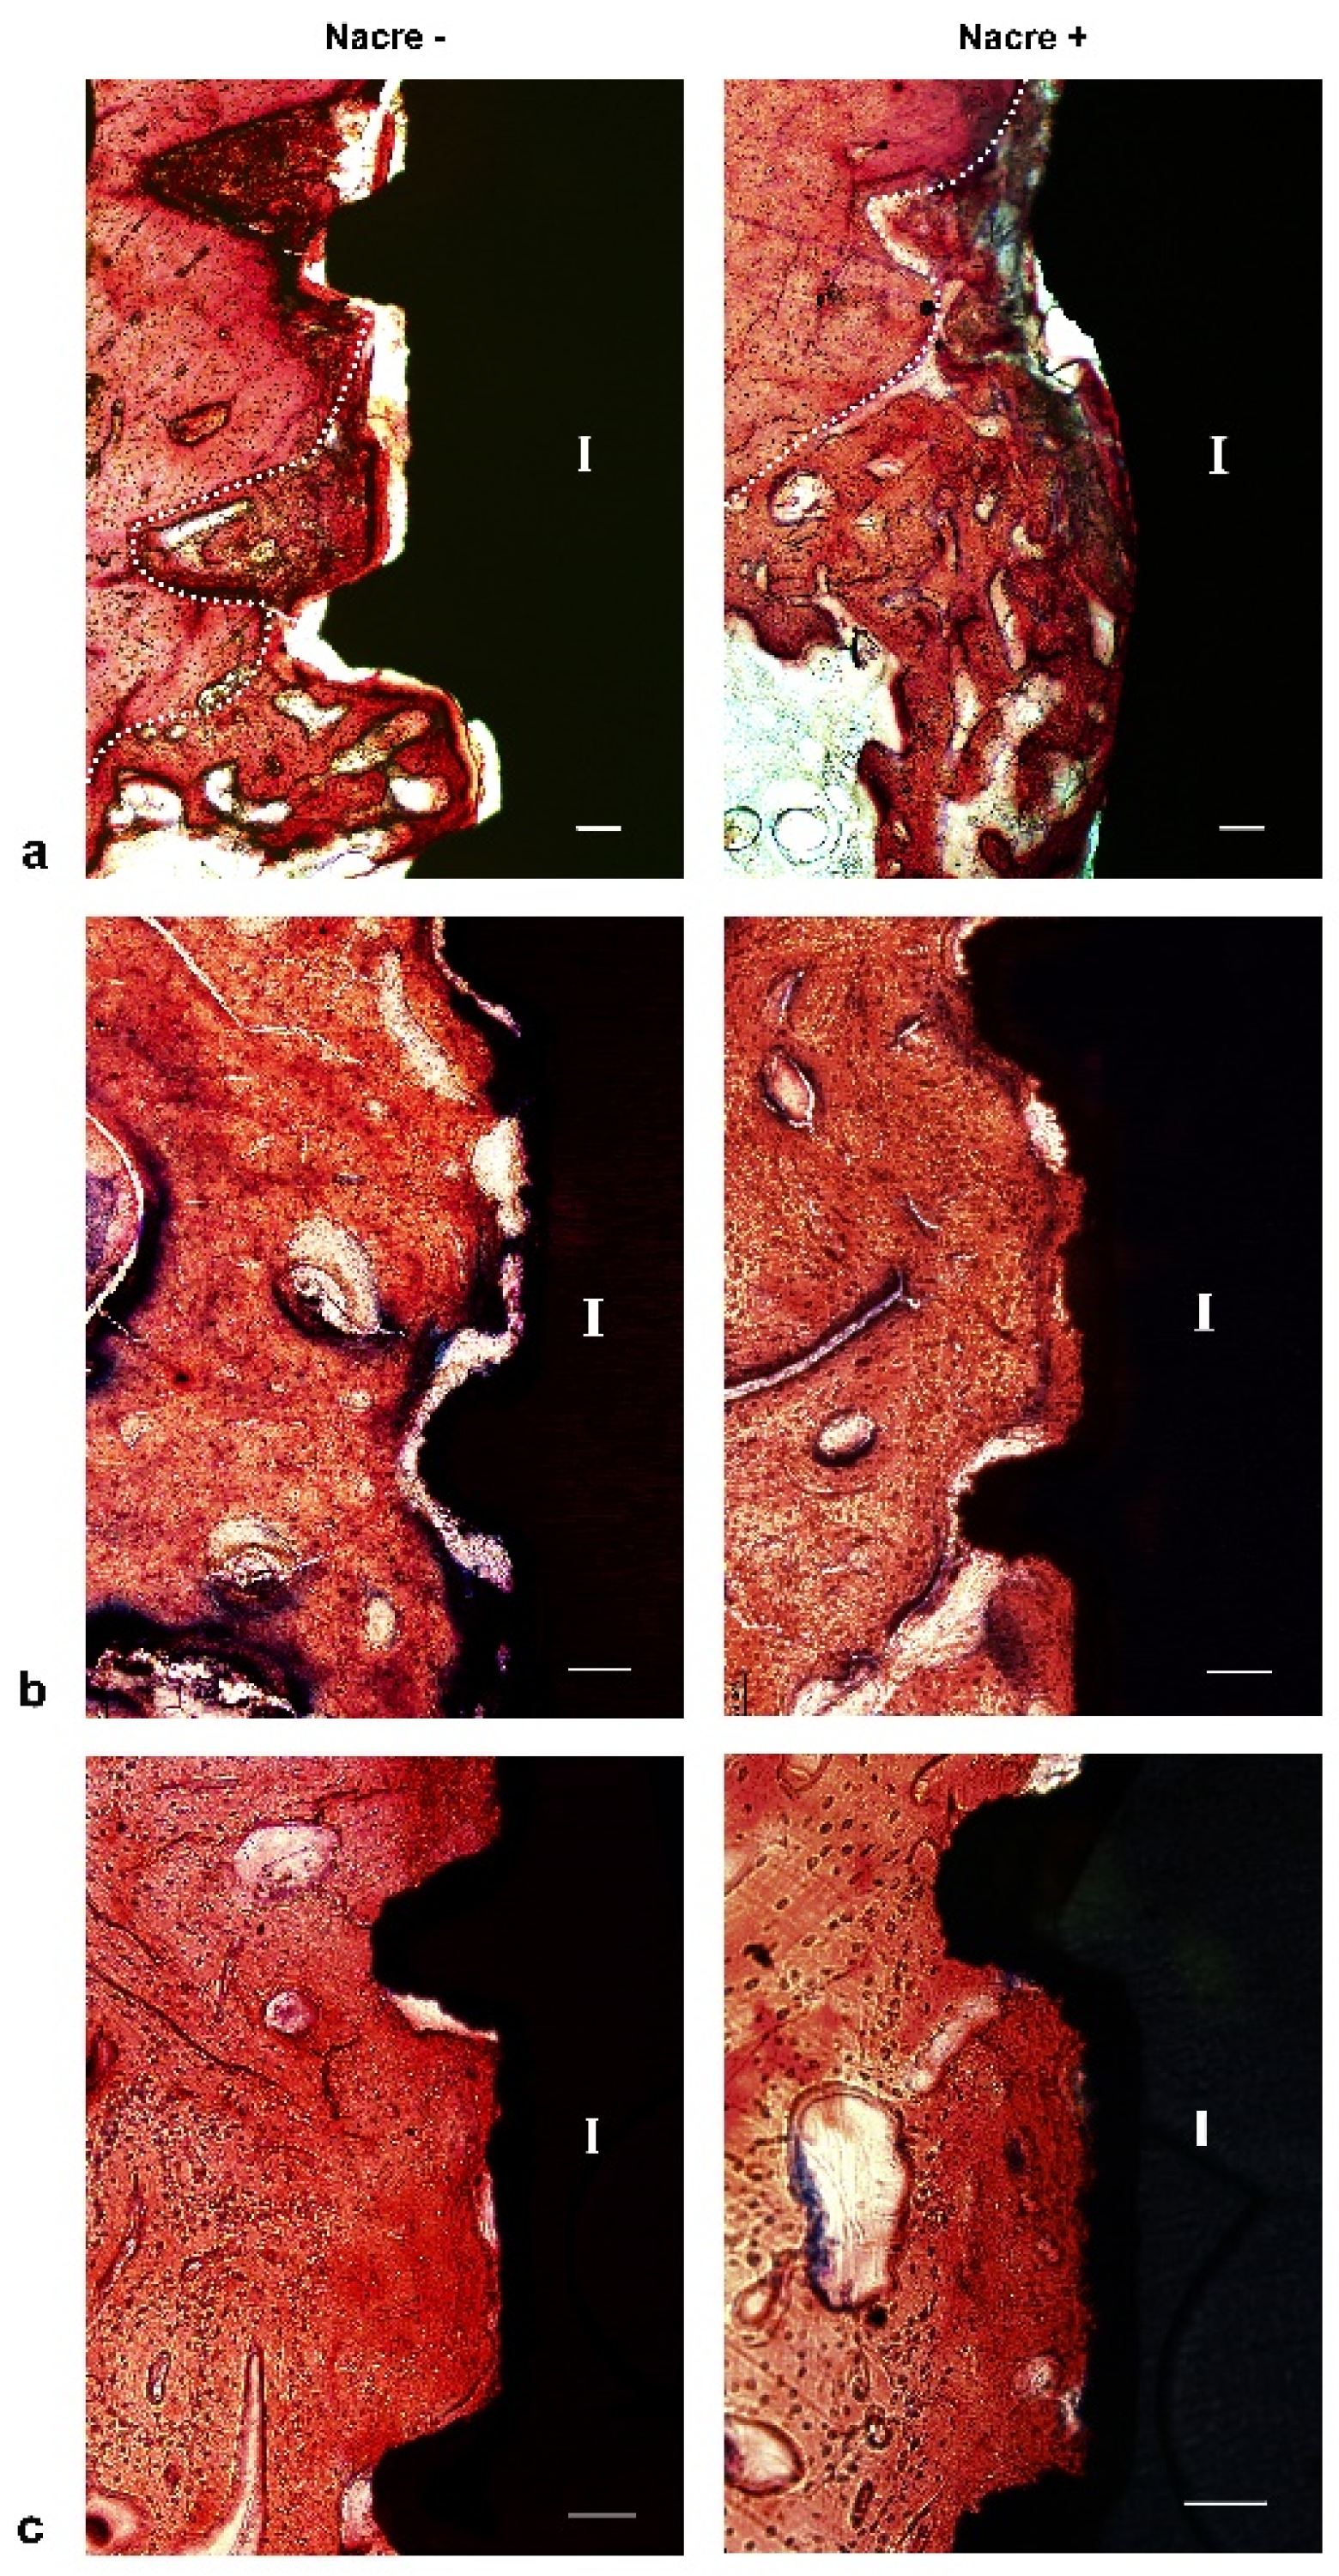

2.3. Histological Study

After two weeks of implantation, histological sections revealed that irregular and disorganized orientations of trabeculae resembling woven bone were formed close to the marrow space and towards the dental implants (Figure 5a). These newly formed trabeculae were more frequently observed after implantation with nacre powder than after implantation without nacre powder. At four weeks after implantation (Figure 5b), woven bone in contact with the implant surface was frequently found in histological sections of dental implants with nacre powder, rather than those without nacre powder. Non-mineralized matrices stained light green-blue were seen in sections of the implantation without nacre powder more than in implantation with nacre powder. It is worth noting that a thin layer of calcified tissue stained with Alizarin red S was found deposited directly on the surface of dental implants with nacre powder. Some bone cells were seen within this tissue (Figure 6). At six weeks after implantation (Figure 5c), it was shown that bone tissue at the site of implantation with nacre powder was in more continuous contact with the dental implant surface than at the site of implantation without nacre powder. Moreover, the circular arrangement of bone cells was more regular between weeks 2 and 4. The results of histochemical staining were consistent with those of micro-CT analyses.

Figure 5.

Light micrographs of XiVE® implant longitudinal sections treated without (left panels) or with (right panels) nacre powder. (a) At week 2. (b) At week 4. (c) At week 6. The dotted line indicates the interface between the old and new bone; I, implant. Bar = 100 µm. Stevenel’s blue and Alizarin red S stain.